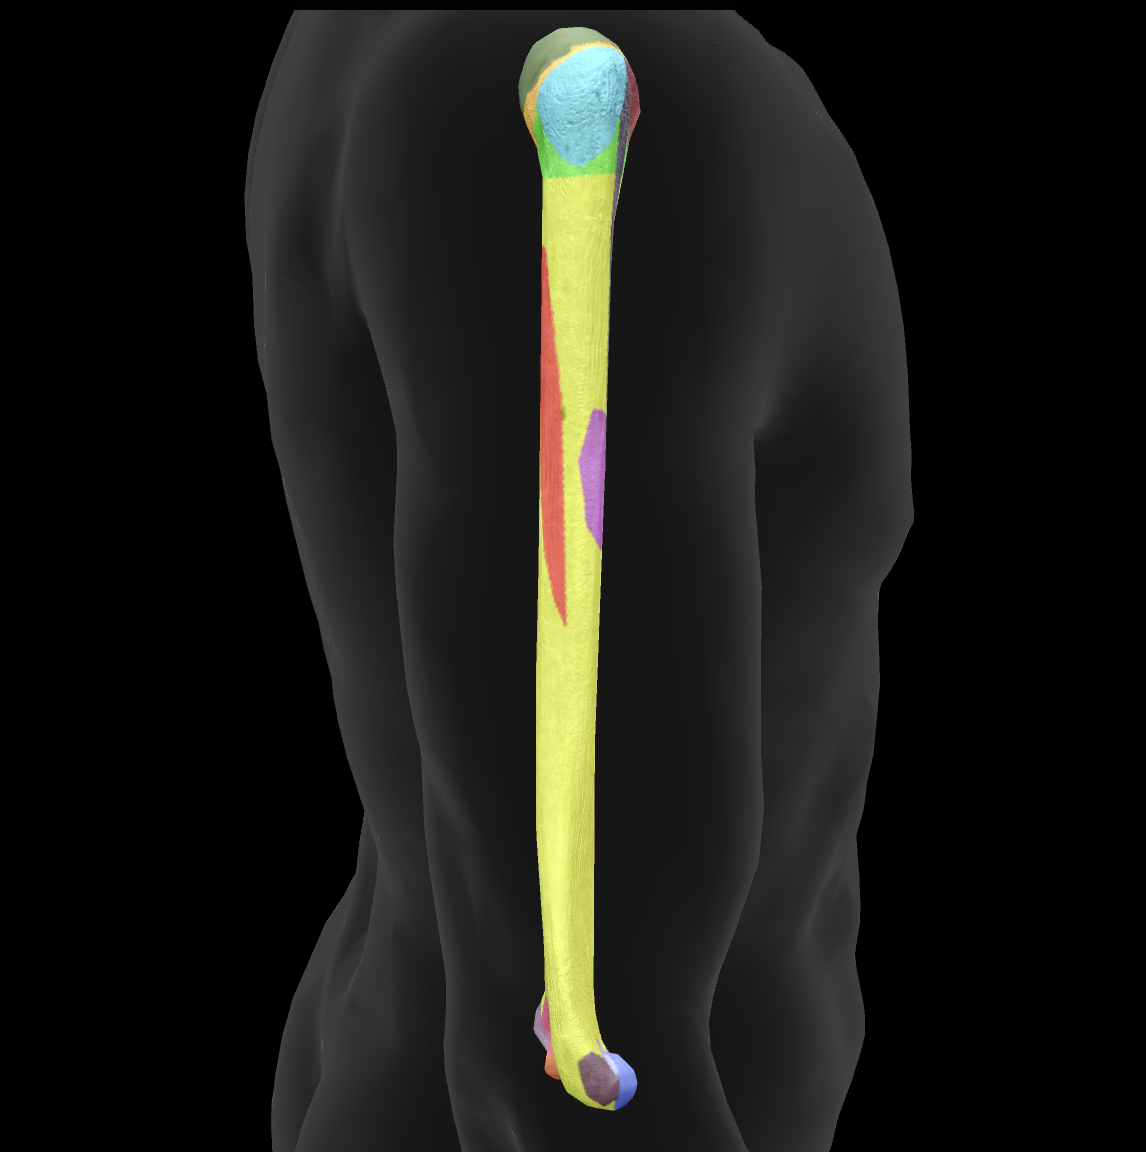

What bone is this?

humerus

What is this boney landmark?

head

What is this boney landmark?

anatomical neck

What is this boney landmark?

surgical neck

What is this boney landmark?

lesser tubercle

What is this boney landmark?

bicipital grove

What is this boney landmark?

deltoid tuberosity

What is this boney landmark?

shaft

What is this boney landmark?

capitulum

What is this boney landmark?

trochlea

What is this boney landmark?

radial fossa

What is this boney landmark?

coronoid fossa

What is this boney landmark?

medial epicondyle

What is this boney landmark?

lateral epicondyle

What is this boney landmark?

greater tubercle

What is this boney landmark?

radial grove

What is this boney landmark?

olecranon fossa

What is this boney landmark?

lateral supracondylar ridge

What is this boney landmark?

medial supracondylar ridge